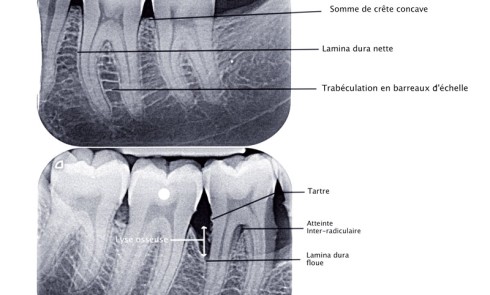

Article réservé à nos abonnés Evolution de l’imagerie en parodontologie

Les maladies parodontales se traduisent par une altération des tissus parodontaux (gencive, ligament alvéolodentaire, cément et os alvéolaire). Leur prise...